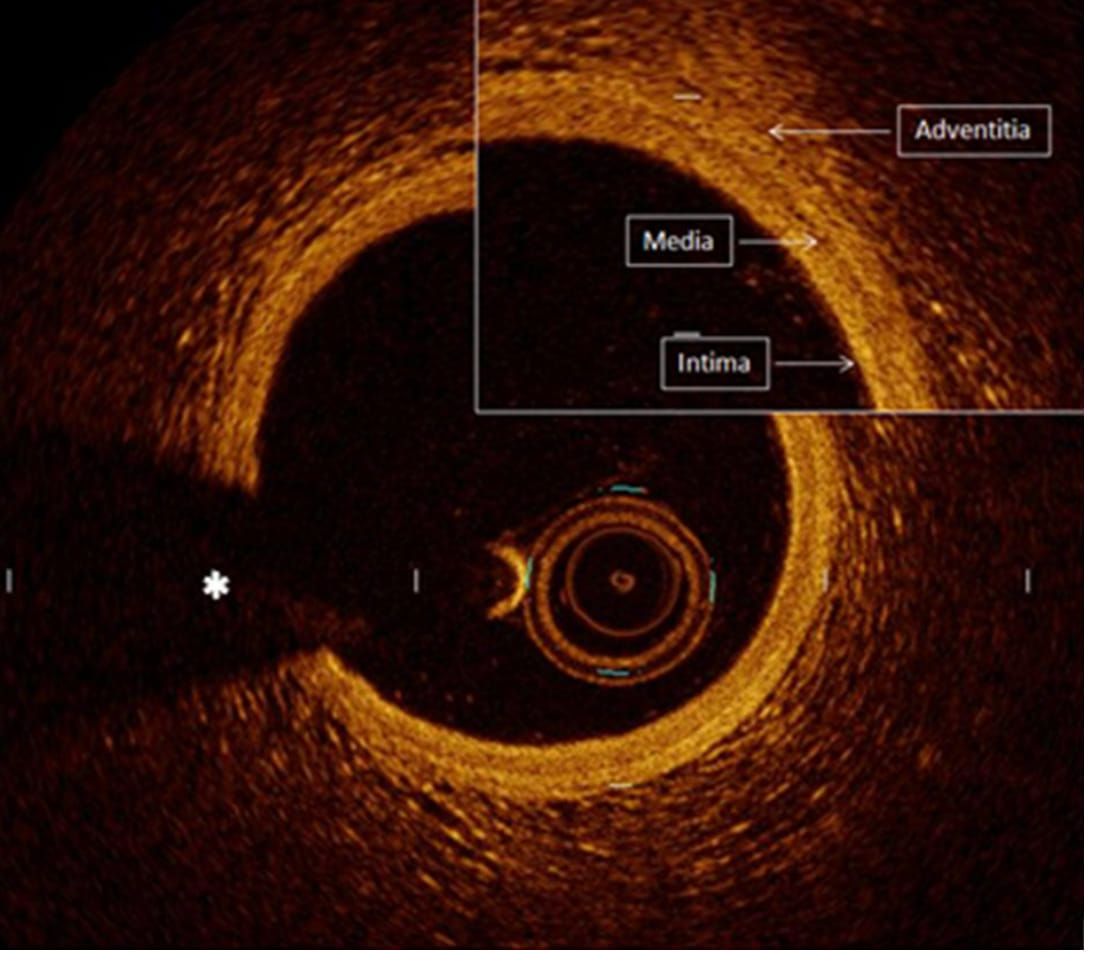

The procedure, Optical Coherence Tomography (OCT), is carried out by inserting a camera-like device which produces three-dimensional images. It is becoming a popular tool among Indian doctors to view the minute details inside the most delicate parts of the human heart.

Doctors define OCT as a high-resolution camera inside the heart’s arteries, which are only two millimetres wide.

“OCT uses a fibre-optic catheter to create cross-sectional images of the artery lumen and wall. It is done while the heart is beating. It gives a high-resolution picture with an effect of showing even a 10 micron tissue,” Chandra explained.